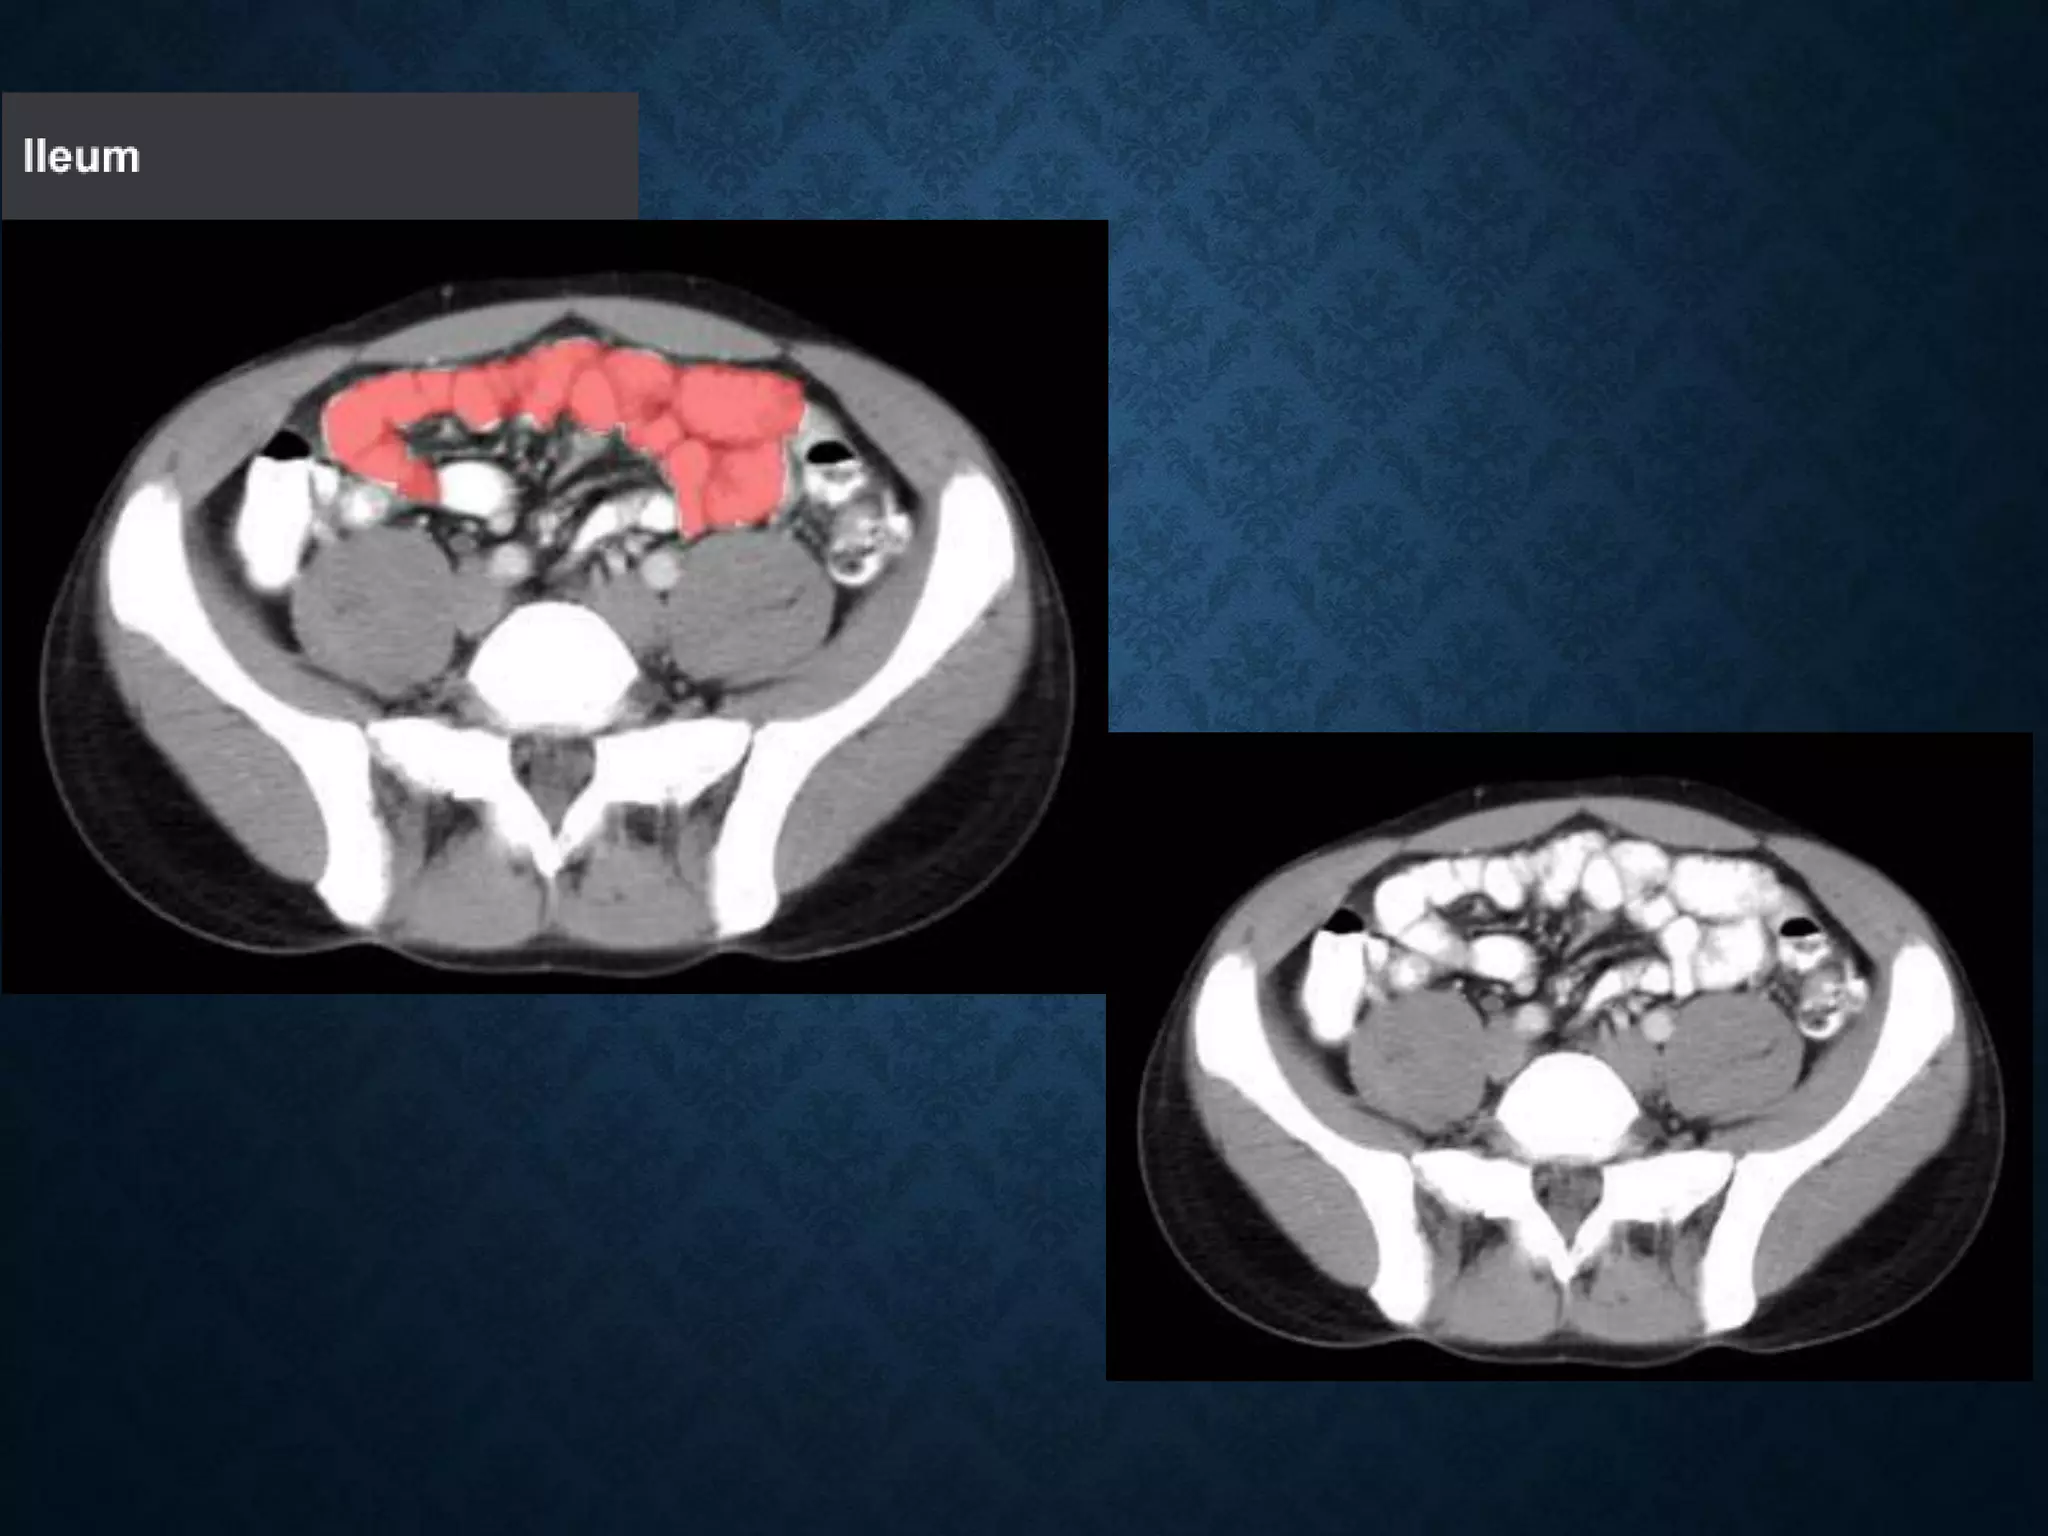

Identify the following structures in the body CT to the right. To view the location of the structure in the image click on

the label at the left and the structure will be indicated in the image. Abdominal CT scans typically begin just above

the diaphragm, so the first slice you see is of the lower chest.

Identify the followingstructures in the body CT to the right. To view the location of the structure in the image click on the label at the left and the structure will be indicated in the image. Abdominal CT scans typically begin just above the diaphragm, so the first slice you see is of the lower chest.